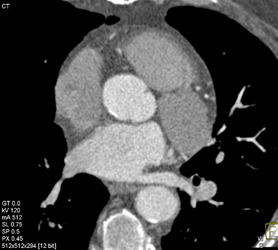

Clot in Right Ventricle